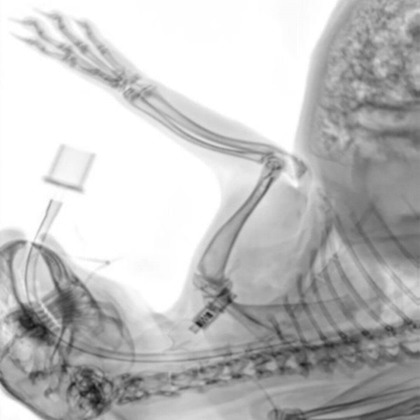

Implants on a sheep bone. The fit of the implants, the progress of healing and fissures on the screw connections are clearly visible.

Implants on a sheep bone. The fit of the implants, the progress of healing and fissures on the screw connections are clearly visible. Image Credit: Scintica Instrumentation Inc